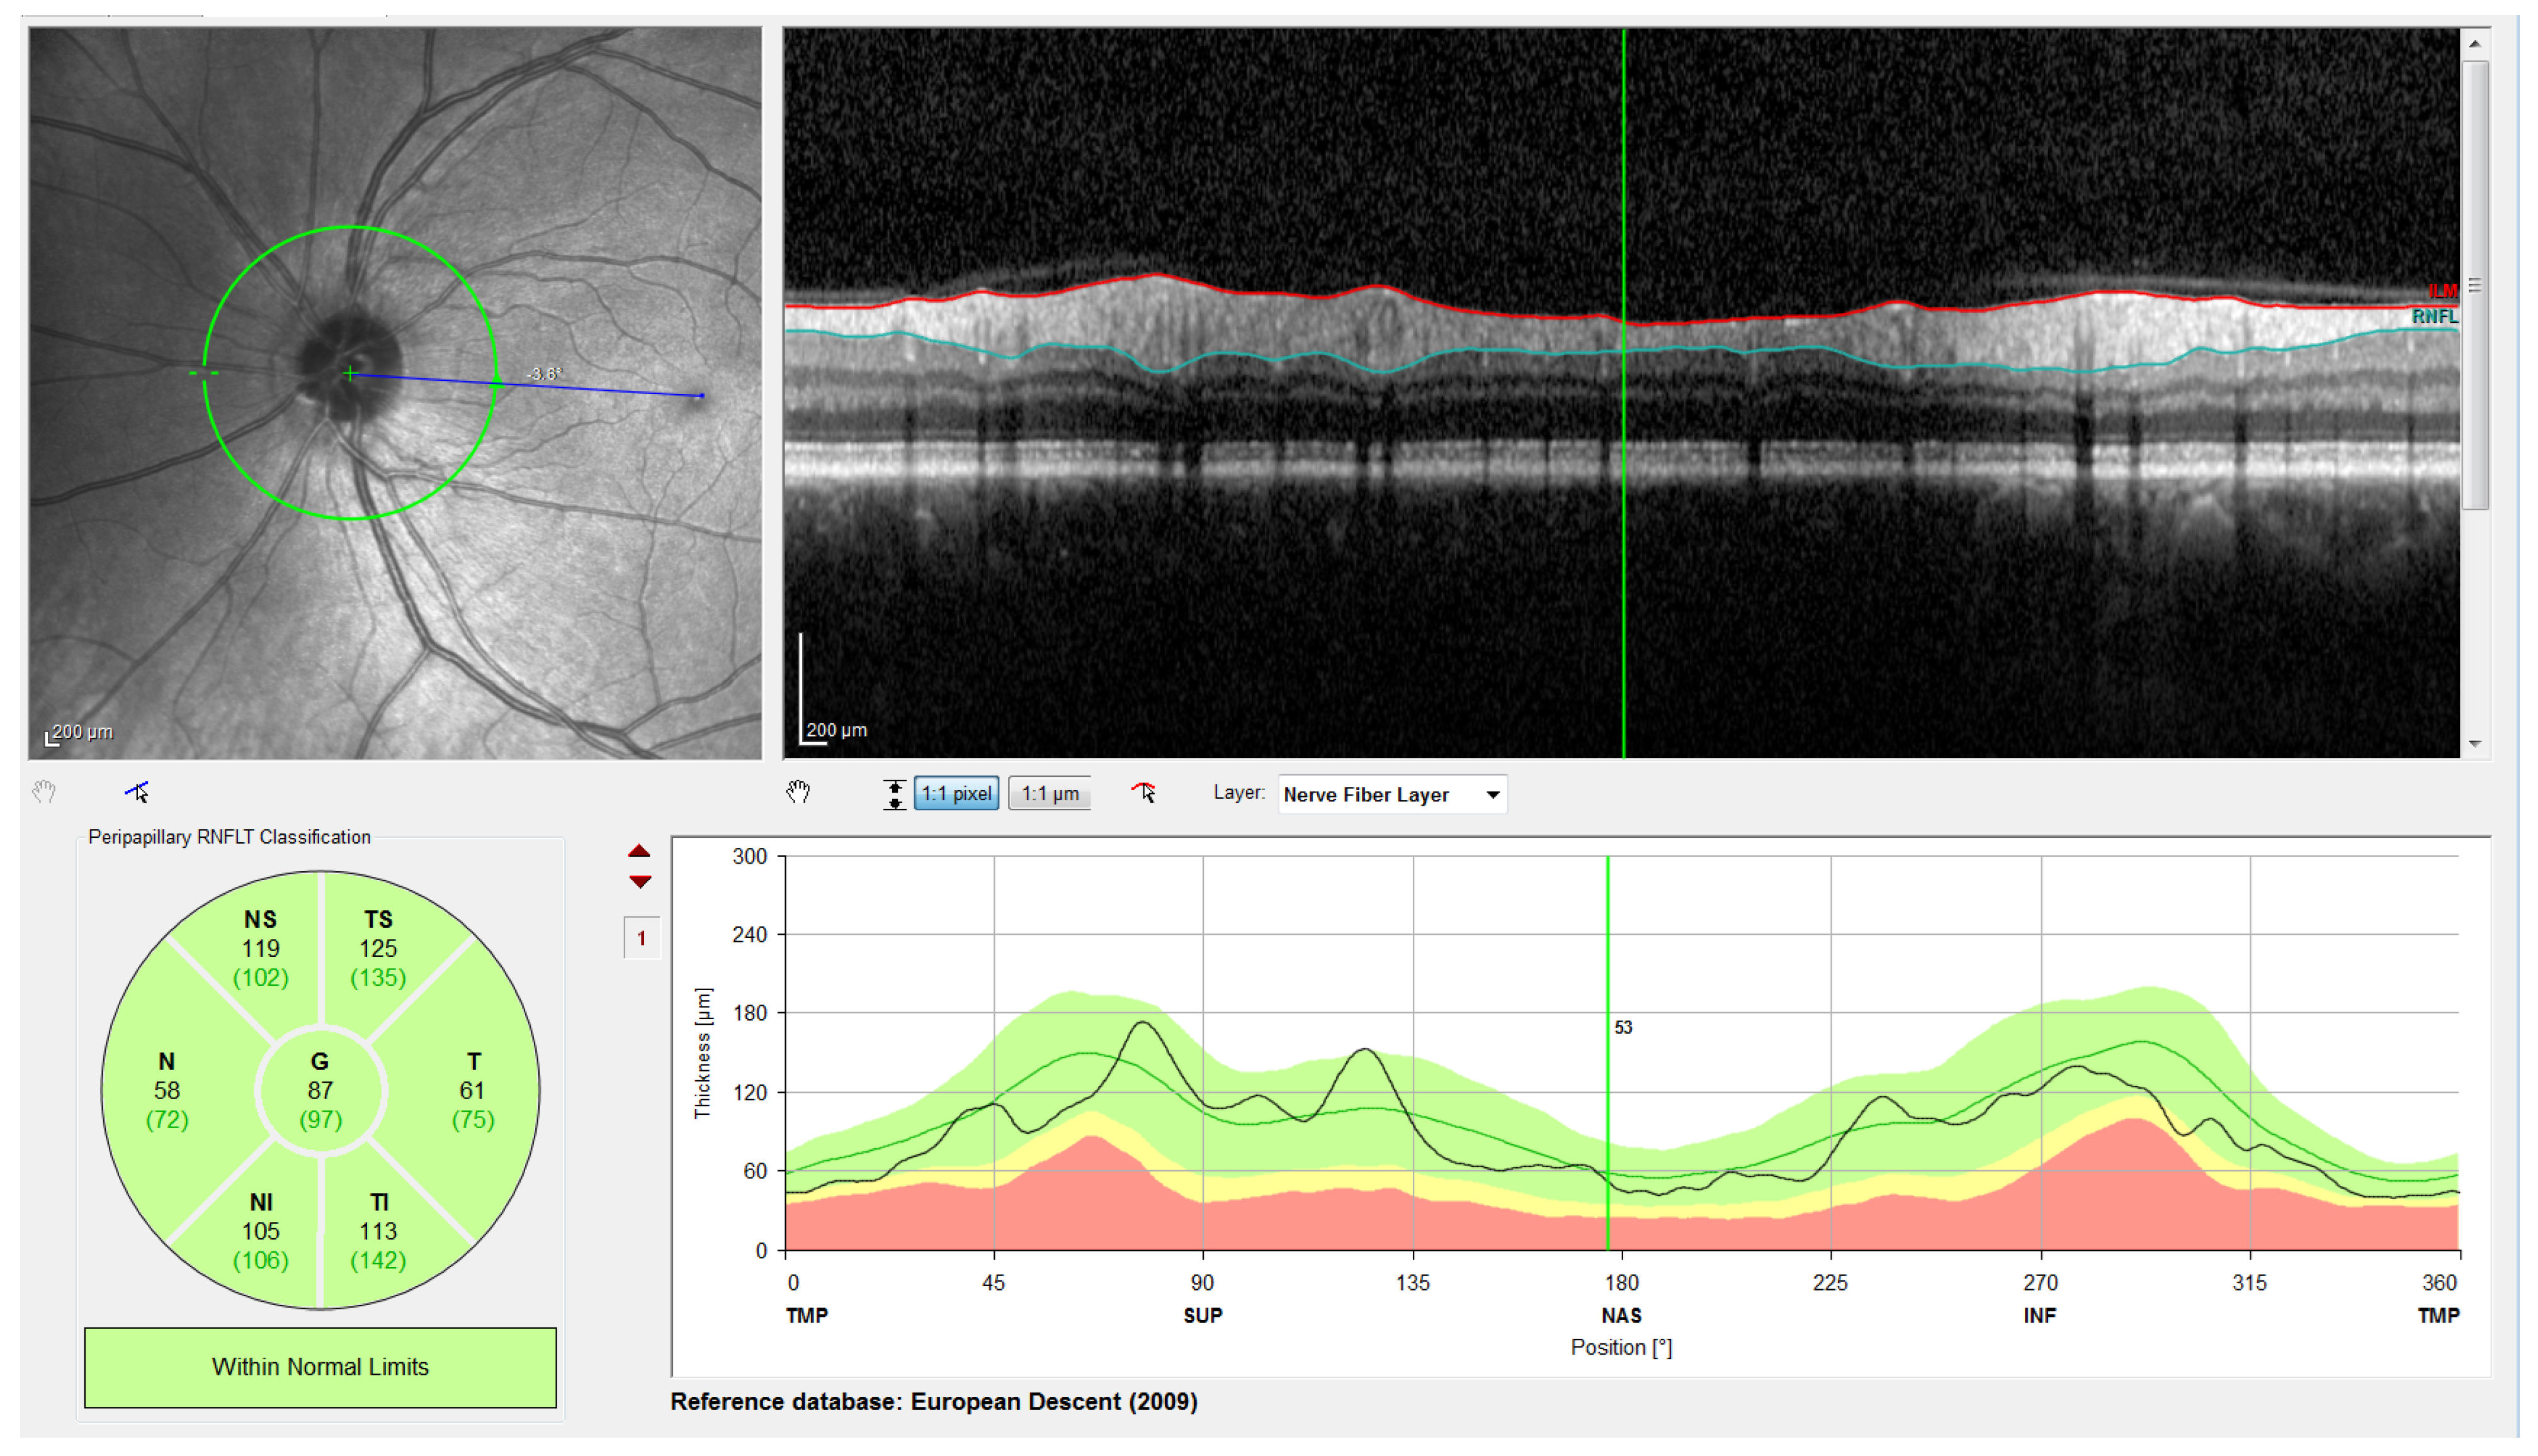

Figure 1.

Peripapillary B-scan OCT centered on the optic disc and its relative axial position with respect to a retinal fundus image. Screenshot taken from the Spectralis OCT device. I, S, N, and T stand for inferior, superior, nasal, and temporal, respectively.

Note that this cylindrical section is projected from polar to Cartesian coordinates for easier processing and analysis. This projection together with its corresponding x- and z-scaling is displayed in the top right of Figure 2. The correspondence between the sectors of the analysis circumference and the x-coordinate of the peripapillary OCT images is gathered in Table 2 and illustrated in Figure 3.

Screenshot provided by the Spectralis software version 6.9.4.0. From left to right and top to bottom: Retinal fundus photography centered on the optic disc (the yellow circle indicates the location of the peripapillary B-scan, which is shown on the right with the segmentation of the RNFL); 2D peripapillary B-scan OCT on Cartesian coordinates; estimated mean values for RNFL layer thickness for the temporal (T), temporal superior (TS), nasal superior (NS), nasal (N), nasal inferior (NI), and temporal inferior (TI) sectors, as well as the overall mean (G); rectified outline of the RNFL with estimated thickness and reference values according to the database European Descent (2009).

The OCT images used in this work have a resolution of 768 × 496 pixels with a z-scaling of 3.87 µm/pixel and a bit depth of 8 bits/pixel in grayscale. The diameter of the peripapillary OCT circumference can be adjusted according to the size of the patient’s eye, varying the horizontal resolution of the OCT accordingly. For instance, a circumference diameter of 3.7 mm corresponds to a x-scaling of 15.21 µm/pixel. Note that only the z-scaling was used for this work, since the main goal is to determine the vertical thickness of the RNFL in the OCT image. The top left of Figure 2 shows the circular tracing of the SLD beam on the retinal fundus image of the eye. This analysis circumference is positioned over the center of the optic nerve (or papilla) as depicted in the figure.